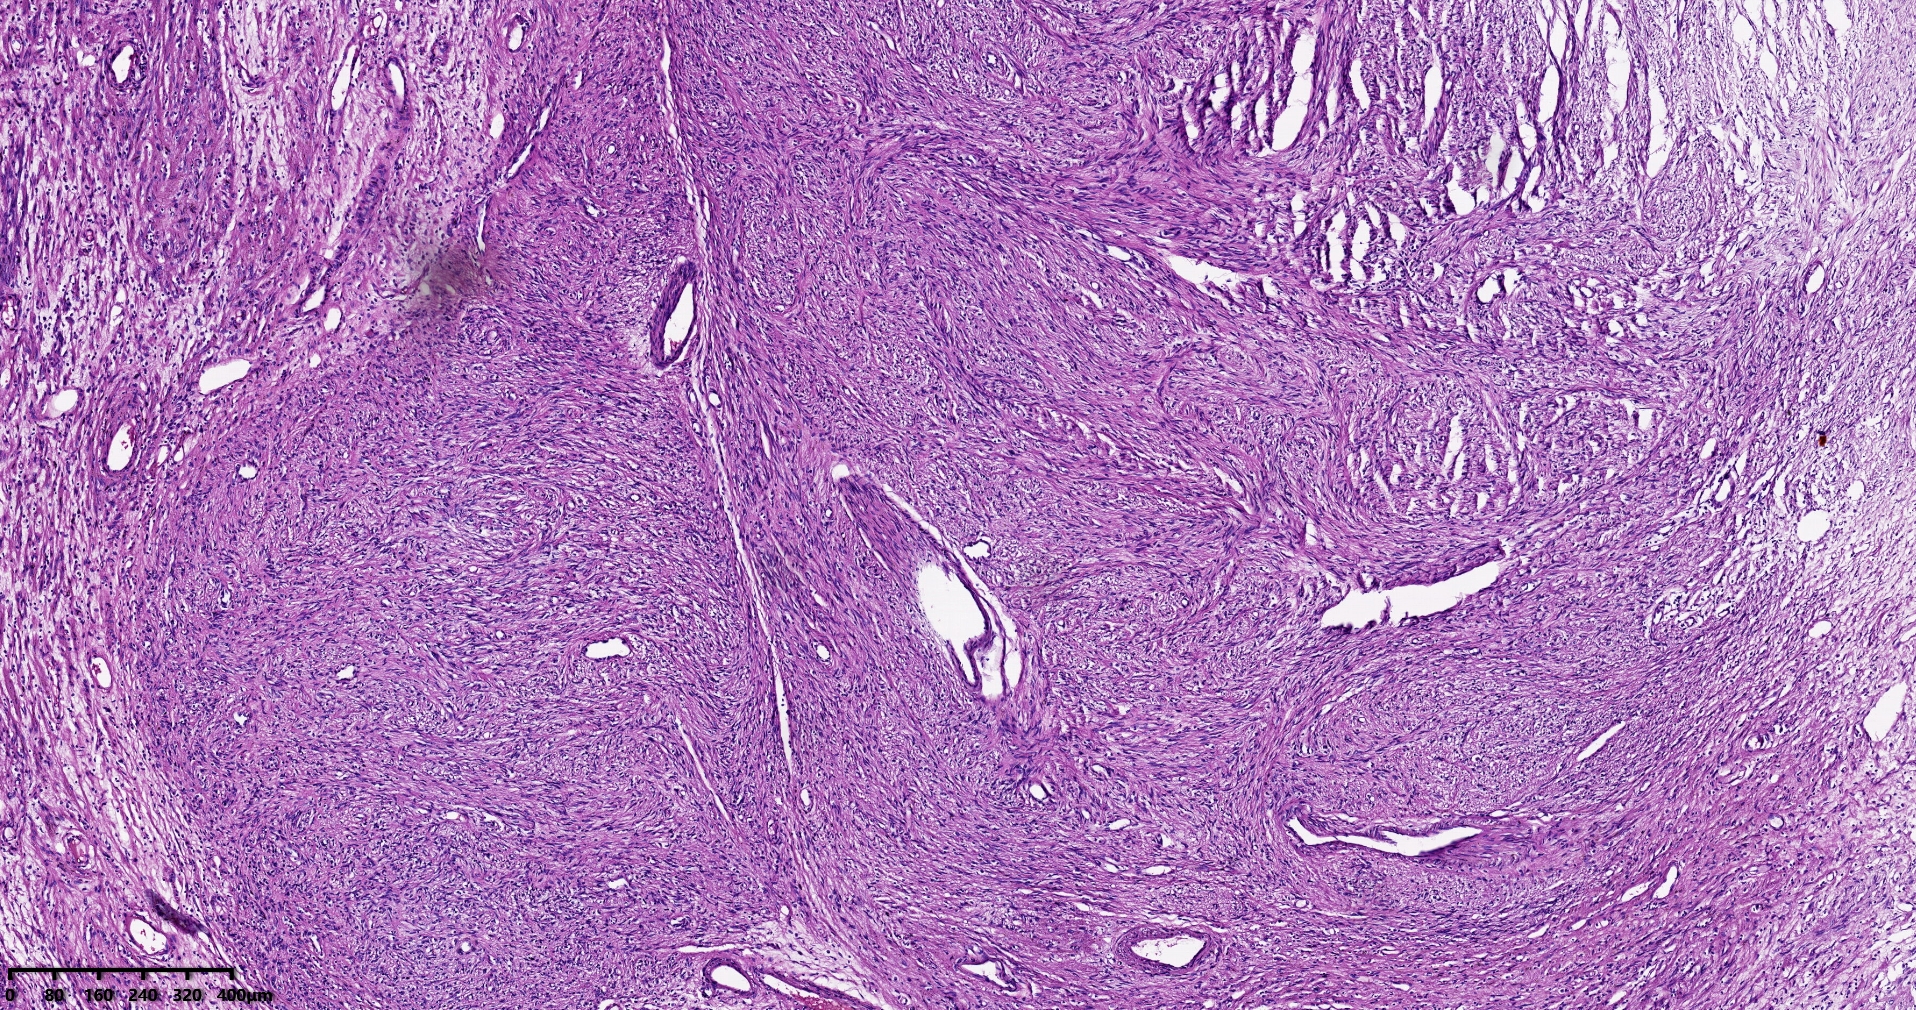

结肠肝曲息肉状肿物,平滑肌瘤?胃肠道间质瘤?炎性纤维性息肉?

性别

男

年龄

56岁

临床诊断

结肠肝曲息肉

一般病史

不详

标本名称

大体所见

灰红色椭圆形息肉一个,直径2.5cm,蒂长0.5cm,切面灰白灰红色,质中。

请路过的老师指教。

考虑间质瘤?

就HE形态而言,间质瘤的可能性要大一些,建议做免疫组化协助鉴别。